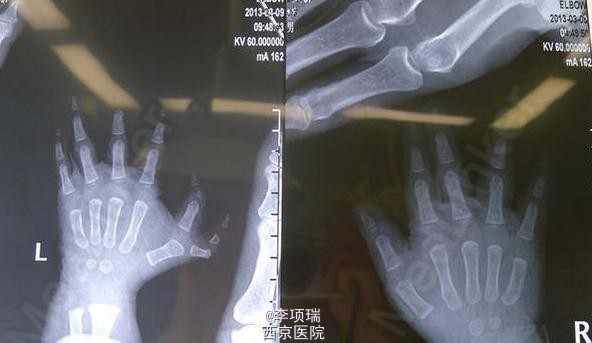

先天畸形:指骨及掌骨同时截骨矫形的多指切除术

患儿,男,1岁两月,左拇多指伴主干指三节拇、IP尺偏、掌骨分叉、MP尺偏。切除多指同时指骨及掌骨截骨矫形克氏针固定。